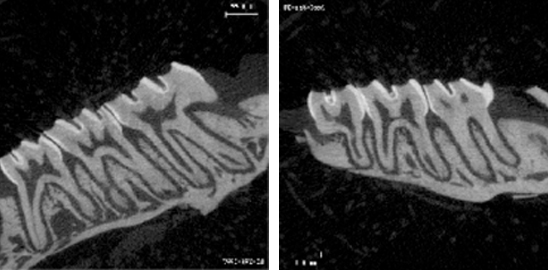

1. 小鼠牙齒高清影像圖

0001

2.小鼠牙齒三維重建

b5bfcb8e5bc50f2ed9f2bc9dabc13643